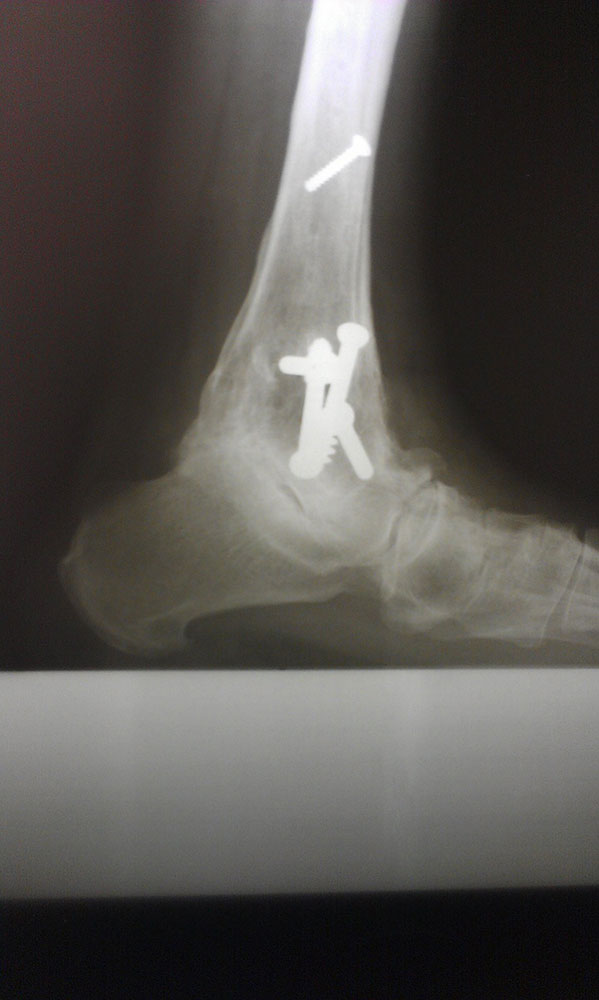

"Surgical misadventure" by another surgeon about 8 years ago. The wrong fixation was used for a flatfoot repair, & the deformity was not corrected. Patient came in with severe foot & ankle pain, with no arch at all. She was unable to play with her grandchild because the pain was so bad, & because she felt unsteady. The old hardware was removed, a lateral calcaneal lengthening osteotomy was performed along with a medial column/1st ray realignment. The ankle was painfully arthritic, & patient elected a total ankle replacement vs. an ankle fusion. She is now able to walk pain free & play with her grandchildren!

Ten years of severe ankle pain with a mal-positioned ankle fusion is now relieved! Patient is now walking with pain-free ankle motion!